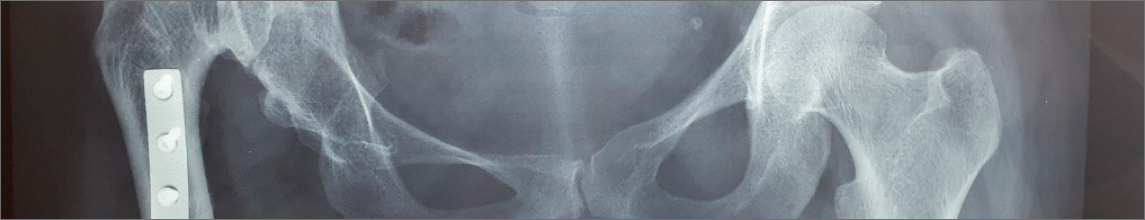

A DDQ é uma condição que afeta a formação adequada da articulação do quadril, podendo causar instabilidade ou deslocamento. O diagnóstico precoce é fundamental e pode ser feito com exames clínicos e ultrassonografia em recém-nascidos. O tratamento varia de acordo com a idade e a gravidade, incluindo o uso de suspensórios de Pavlik, gessos ou cirurgias corretivas para garantir a saúde articular e prevenir complicações no futuro, como artrose.

Displasia do quadril: Como o diagnóstico precoce pode mudar a vida do seu filho.

A Displasia do Desenvolvimento do Quadril (DDQ) é uma condição que afeta a articulação do quadril, caracterizada pela incongruência entre a cabeça do fêmur e o acetábulo. Essa condição é